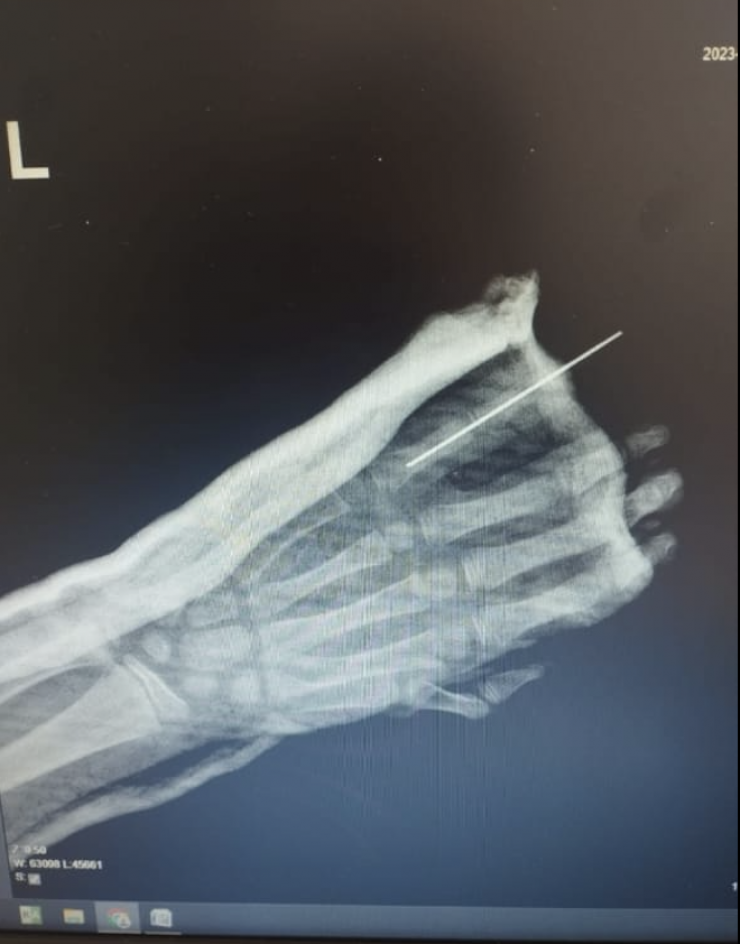

9-летнему мальчику пришили пятый палец руки, отчлененный в результате уличной травмы.

Операция длилась непрерывно около 5 часов. Это очень кропотливая работа. Хирурги под операционным микроскопом сшивали ткани и сосуды, соединяли поврежденные пальцевые артерии, нервные волокна очень малого диаметра. Были восстановлены кость, сухожилия, вены и кровообращение в присоединенном пальце.

Фото предоставлено пресс-службой ДГКБ № 2 Алматы

"Для проведения такой операции необходима современная микрохирургическая техника: требуется микроскоп, микрохирургический инструментарий и очень тонкий шовный материал, который сложно увидеть невооруженным глазом, все это имеется у нас во 2-й детской больнице. Нам пришлось шить сосуды диаметром 1,2 миллиметра. Без должной подготовки, оборудования, инструментов и расходных материалов проведение таких операций невозможно", - рассказал заведующий отделением травматологии ДГКБ № 2 Ерлан Садырбалин.

Профессионально выполненная реплантация позволила избежать возможных рисков, вернуть подвижность, чувствительность поврежденной части кисти. В течение 8 дней мальчик получал стационарное лечение, палец полностью прижился, рассказали хирурги.